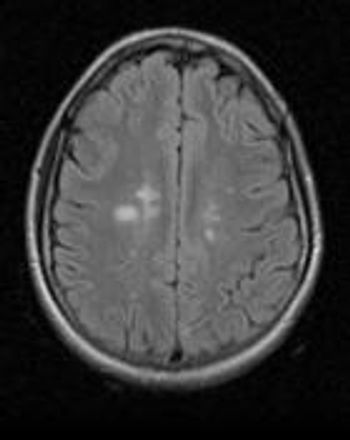

Determining who is at risk for MS remains difficult, and symptoms may take time to develop even in patients who already have some destroyed myelin. MRI may help.